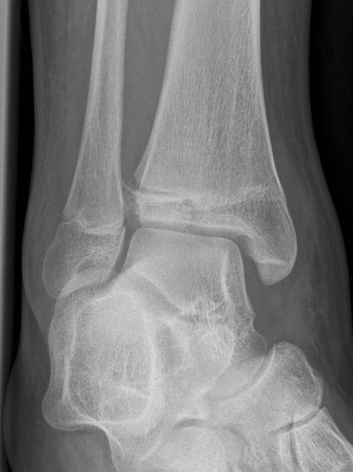

Xray

AP xray: Salter-Harris type III / Tillaux

Lateral xray: Salter-Harris Type II